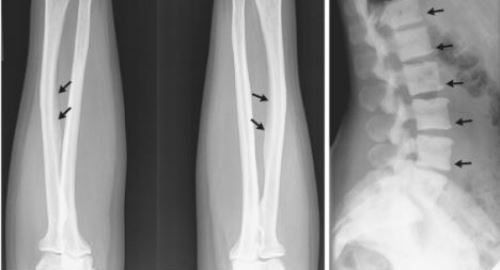

На III стадии развития патологии, усиливаются болевые ощущения в позвоночнике и суставах. Больному становится трудно выполнять свои повседневные обязанности. Продолжается разрушение зубной эмали. Обнаруживается повышенное содержание фтора в моче, наблюдаются утолщения костей.

Диагностика флюороза скелета обычно включает в себя рентгенографию, которая позволяет выявить изменения в костной ткани, а также анализы на содержание фтора в организме. Врач может также провести опрос о симптомах и истории болезни пациента для более точного определения состояния.